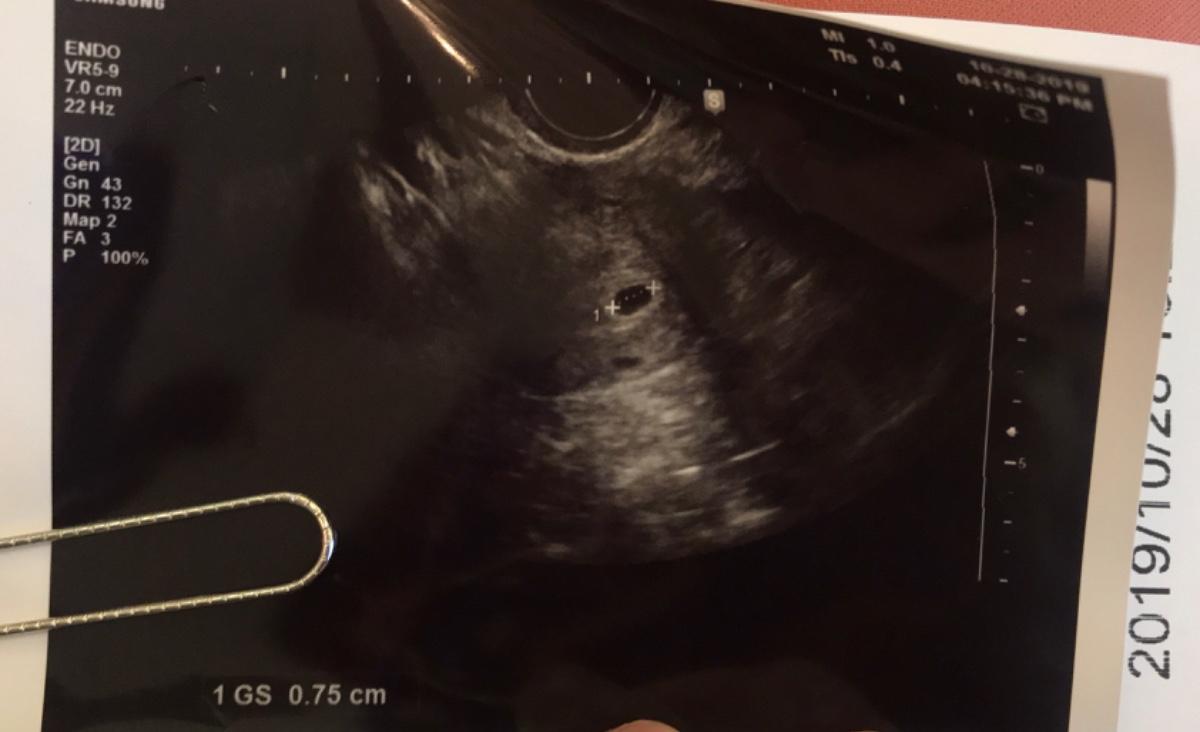

果然⋯經過精密的檢測,我⋯真的「有了」,醫生說約4週左右~目前只是一個小小的胚胎喔~